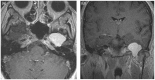

Intracranial trigeminal schwannomas are rare tumors. Patients usually present with symptoms of trigeminal nerve dysfunction, the most common symptom being facial pain. MRI is the imaging modality of choice and is usually diagnostic in the appropriate clinical setting. The thin T2-weighted CISS 3D axial sequence is important for proper assessment of the cisternal segment of the nerve. They are usually hypointense on T1, hyperintense on T2 with avid enhancement post gadolinium. CT scan is supplementary to MRI, particularly for tumors located in the skull base. Imaging plays a role in diagnosis and surgical planning. In this pictorial essay, we retrospectively reviewed imaging findings in nine patients with pathologically proven trigeminal schwannoma. Familiarity with the imaging findings of intracranial trigeminal schwannoma may help to diagnose this entity.